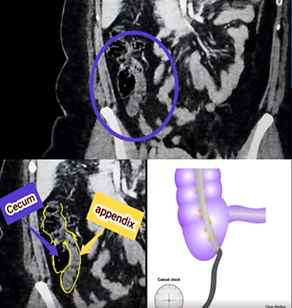

4. Locations of the Appendix

(Radiologically important as they alter both symptoms and signs)

Retrocecal: Most common (up to 65%), difficult to visualize with US, CT is more useful

​​​​​​​​Pelvic: Adjacent to bladder; may present with dysuria or pelvic pain

Subcecal: Beneath the cecum, easy US window

Paracecal: Medial or anterior to the cecum

Preileal / Postileal: Rare; may mimic right upper quadrant pain

Promontory: Near the pelvic promontory, atypical location

Retrocecal

Paracecal

Subcecal

Promontory

Pelvic

💡💡💡💡If you want to see the detailed, annotated axial and coronal CT images of the cases shown in the pictures, watch the video.

6. CT Findings (Gold standard, especially in atypical cases and obese patients)

Blind-ended, dilated appendix (>6 mm)

Wall thickening and contrast enhancement

Increased density (fat stranding) in periappendiceal fat planes

Appendicolith hyperdense (80–140 HU)

Complications: abscess, free air (perforation), phlegmon

CT findings of Appendicitis